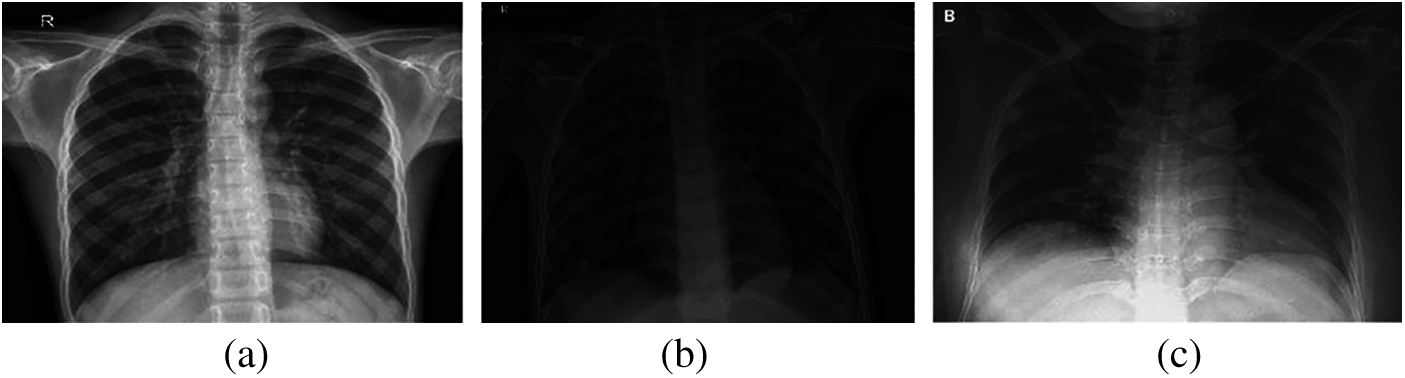

Over the past two decades, automatic disease diagnosis has been used in the medical sciences to provide fast and accurate results. Medical imaging has become one of the most important medical sciences which are based on visualization diagnosis. It has captured researchers’ attention through different modalities such as X-ray, CT, and MRI to diagnose different diseases. The mechanism of image acquisition plays a role in the correct diagnosis of the COVID-19 pandemic from the acquired images [2–5]. X-ray beams are directed towards the lung, as X-ray imaging depends on the interaction between photons and electrons, resulting in different absorption levels due to densities of tissues classes [6–11]. Hence, there is a difference between normal lung images, pneumonia images, and COVID-19 images, as illustrated in Fig. 1.

Figure 1: (a) Normal, (b) pneumonia, and (c) COVID-19 X-ray images